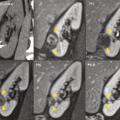

Pour chaque patient, un bilan d’hémostase est systématiquement réalisé avant la procédure. Pour les patients prenant des anticoagulants oraux, un relais par héparine de bas poids moléculaire est réalisé. Pour les antiagrégants plaquettaires, seul le clopidogrel doit être interrompu 5 jours avant. Le patient reçoit une prémédication par 1 g de paracétamol intraveineux 30 minutes avant la procédure. Il reste hospitalisé une nuit, mais une prise en charge ambulatoire est possible.La cryothérapie est réalisée sous anesthésie locale à l’aide d’un mélange de lidocaïne et de ropivacaïne. Contrairement à la radiofréquence ou aux micro-ondes où une seule électrode est insérée, la cryothérapie nécessite de mettre en place plusieurs aiguilles (cryoprobes) espacées au maximum de 15 mm afin de couvrir la totalité de la tumeur (fig. 1 ). Plus la tumeur est grosse, plus le nombre d’aiguilles à introduire est important. Il existe des abaques permettant de déterminer le nombre d’aiguilles optimal en fonction de la taille de la tumeur. Néanmoins, l’indication principale étant des tumeurs de stade T1a (< 4 cm de diamètre), le nombre moyen d’aiguilles est de 3, avec des extrêmes entre 2 et 5. Une injection de CO2 (carbodissection) ou de sérum physiologique (hydrodissection) est parfois nécessaire entre le rein et les organes adjacents afin de les éloigner de la zone d’ablation et les protéger.Les aiguilles sont mises en place sous tomodensitométrie et on vérifie leur bon positionnement. La dose délivrée lors d’une cryoablation rénale est inférieure aux niveaux de référence de dose recommandés pour une tomodensitométrie abdominale. Le traitement consiste en deux phases de cryoablation de 10 minutes entrecoupées d’une phase de réchauffement passif de 10 minutes également. L’effet cryogénique est obtenu par expansion d’un gaz (l’argon) dans une chambre de décompression de 2 à 4 cm de long située à l’extrémité de l’aiguille. Les températures minimales obtenues au contact de l’aiguille sont proches de -100 °C, en sachant qu’en moyenne la température de la tumeur se situe à -40 °C. La tomodensitométrie permet une excellente visualisation de la boule de glace, ce qui permet de monitorer l’ablation tout au long de la procédure. La boule de glace ainsi créée doit englober en totalité la tumeur et la dépasser de 5 mm afin d’avoir des marges de sécurité (fig. 2 ).6 En effet, le bord de la boule de glace est à l’isotherme 0 °C, qui n’est pas létal pour les tissus.Après traitement, le suivi des patients s’effectue par tomodensitométrie ou par imagerie par résonance magnétique (IRM), typiquement à 1 mois, 3 mois, 6 mois et 1 an, puis tous les ans. La zone d’ablation se rétracte progressivement et se fibrose, sans tumeur résiduelle visible (fig. 3 ). Pour les tumeurs de moins de 2 cm, le zone d’ablation disparaît parfois en totalité, laissant juste une encoche à la surface du rein (fig. 4 ). Les effets secondaires sont rares, la cryoablation étant mieux tolérée que les techniques d’ablation fondées sur le chauffage des lésions, en particulier pour les lésions proches de la voie excrétrice.7